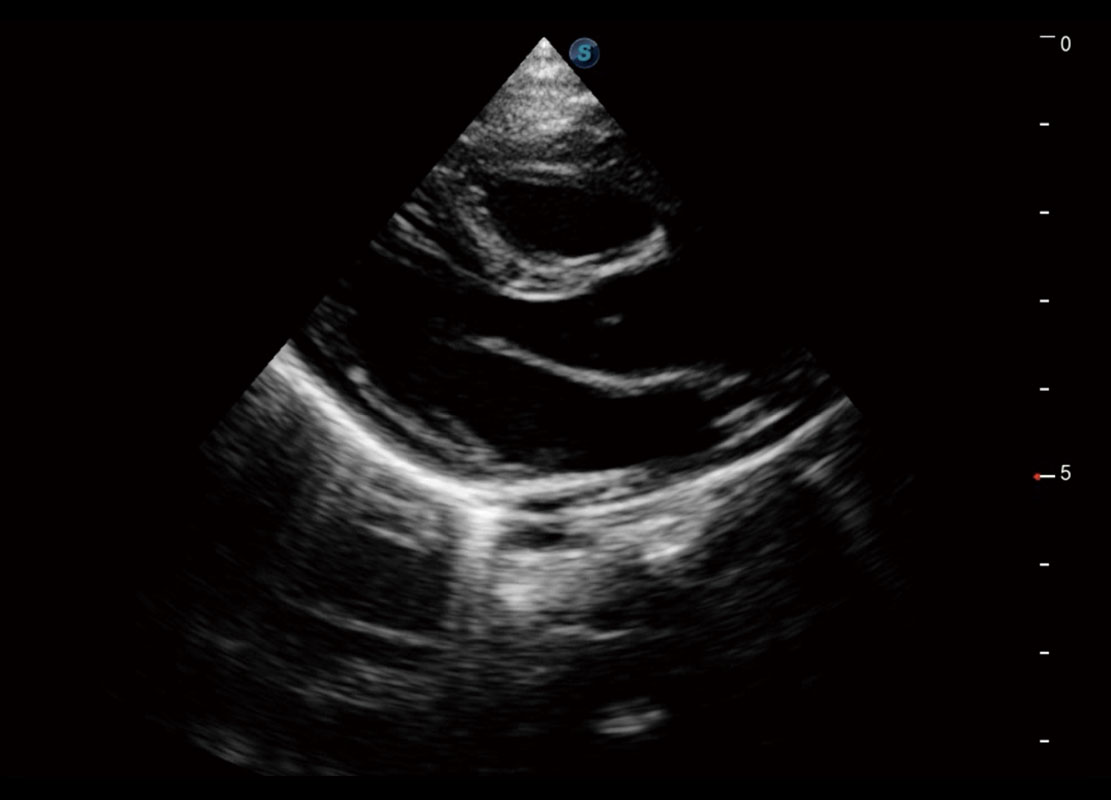

P60搭載一系列胎兒心臟成像技術(shù),實(shí)現(xiàn)精細(xì)的胎兒心臟評(píng)估。

四腔切面

四腔心血流

右室雙出口

胎心容積成像